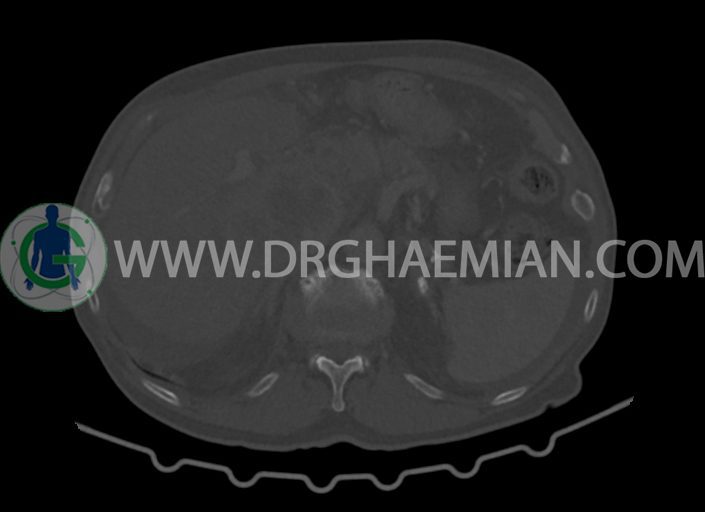

در سی تی اسکن اسپیرال شکم و لگن با کنتراست خوراکی و وریدی (مولتی دیدکتور 16 با مقاطع ظریف و بازسازی های ساژیتال و کرونال) :

-توده ی بزرگ با حدود لبوله به ابعاد 89x87x76mm در لوب چپ کبد همراه با گسترش اکستراکپسولار و

شواهد آتروفی لوب جپ کبد

-مایع آسیت با حجم Mild در ساب فرنیک دو طرف ، ساب هپاتیک و ساب اسپلنیک و اینترلوپ لگنپ